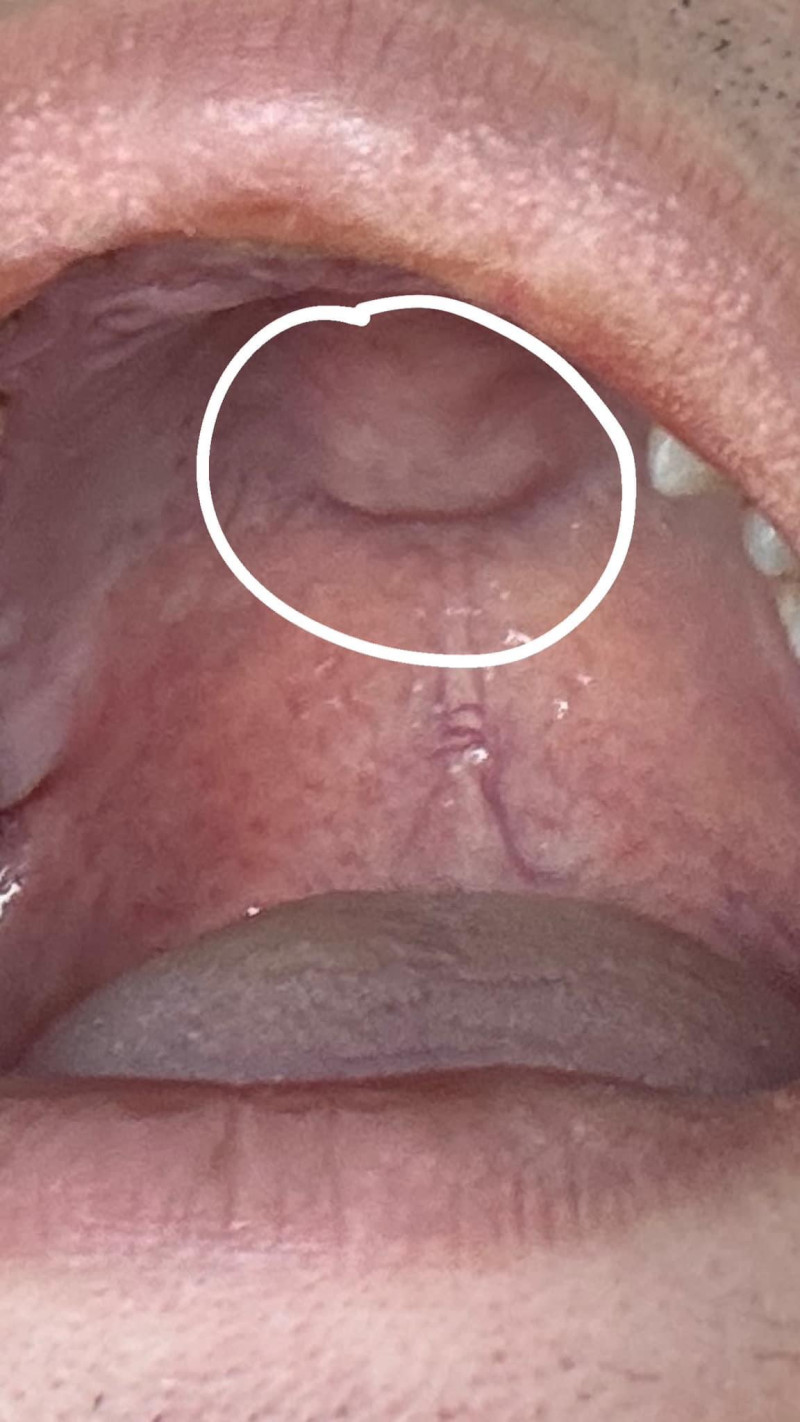

• Bác sĩ Trương Anh Hào

Sinh viên K45 Đại học y dược Cần Thơ

Chào bạn, tình trạng bạn nên đến các cơ sở y tế để được khám và tư vấn trực tiếp, cạo vôi răng nhằm vệ sinh răng miệng kèm sử dụng thêm nước súc miệng chuyên dụng nhé!